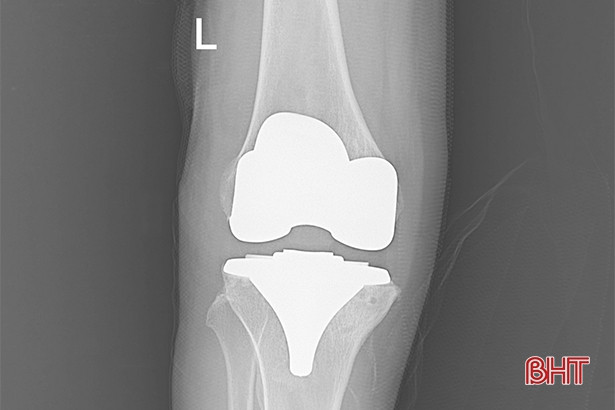

Hình ảnh chụp sau thay khớp của bệnh nhân L.

Bệnh nhân Trương Thị L. (72 tuổi, xã Thạch Bàn, Thạch Hà) vừa nhập viện và điều trị tại Khoa Chấn thương chỉnh hình - bỏng. Trước đây, bệnh nhân bị đau khớp gối trái và điều trị tại nội khoa đã lâu. Tuy nhiên, thời gian gần đây, khớp gối trái bị đau nhiều hơn, cứng khớp, không thể đi lại được.

Sau khi nhập viện và được các bác sỹ thăm khám, hội chẩn, bệnh nhân được chẩn đoán thoái hóa khớp gối độ IV, có chỉ định phẫu thuật thay khớp gối toàn phần.

Sau phẫu thuật, sức khỏe bà L. đã ổn định.